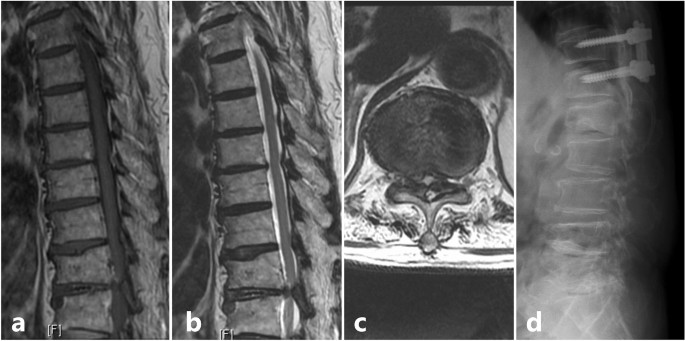

For cervical lesions, anterior cervical discectomy and fusion (ACDF) was performed for 15 patients, Hirabayashi’s laminoplasty for 5 patients with OPLL, combined ACDF and cervical laminectomy for 1 patient and cervical laminectomy for 3 patients. For thoracic stenosis, 4 patients underwent posterior decompression and stabilization (Fig. 3). Among the 18 patients with tandem spinal stenosis, all were treated with staged surgery. The cervical lesion was treated first with procedures listed above in 10 patients while coexisting thoracic or lumbar lesion were treated first in 8 patients. Patients were on rehabilitation and rest for a period of 6 weeks. After which, they were allowed to carry on with household activities. Four of those patients with tandem spinal stenosis developed radiculopathy and objective lower limb weakness pertaining to the course of a particular nerve after a mean duration of 7.2 ± 1.5 months, which required decompression, interbody fusion and stabilization of the lumbar spine.

Scenario of a patient with solitary thoracic lesion who presented with category 2 signs; (a) Sagittal T1 weighted MRI showing an Ossified Ligamentum Flavum (OLF) at T11-T12 level; (b) Sagittal T2 weighted MRI; (c) Axial T2 weighted MRI showing the significant stenosis caused due to the OLF at T11-T12 level; (d) Post decompression and stabilization lateral view X-ray image.